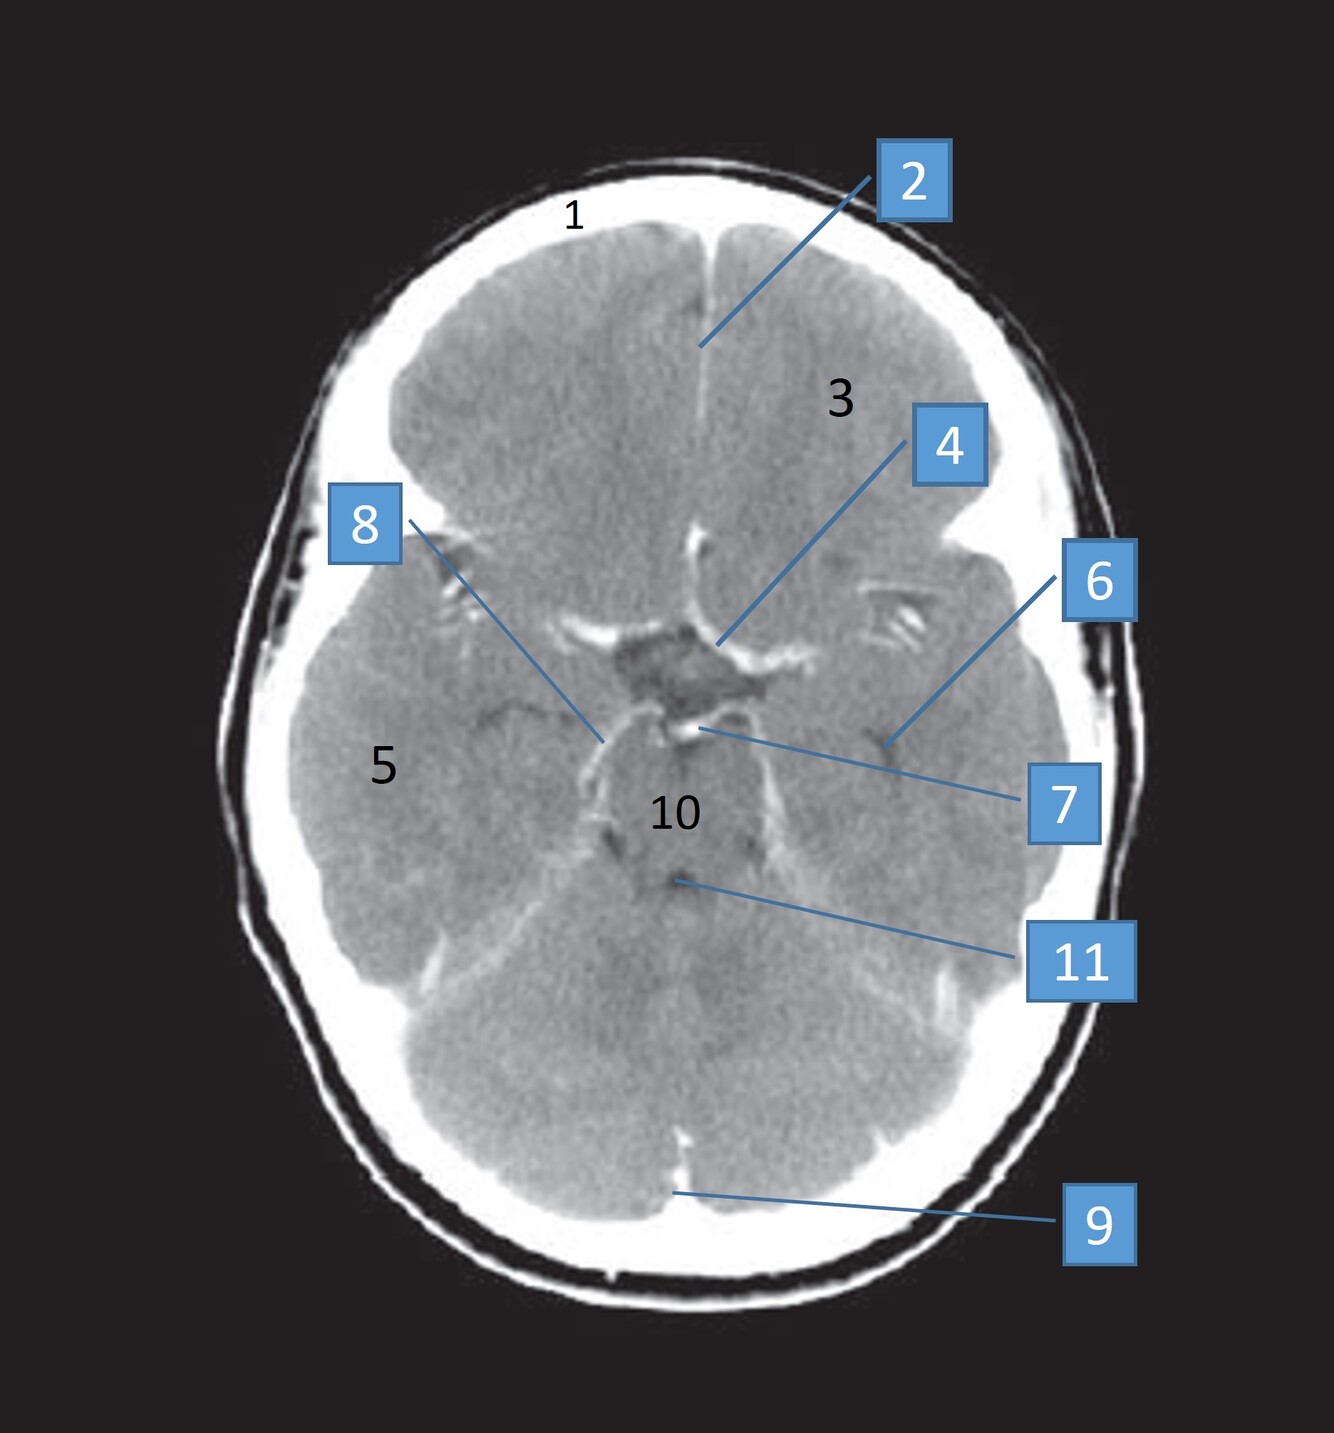

1

Q

Label 1-5

A

1. Rt putamen

2. Rt globus pallidus

3. Rt Caudate nucleus

4. Lt Insula

5. Choroid plexus of left lateral ventricle